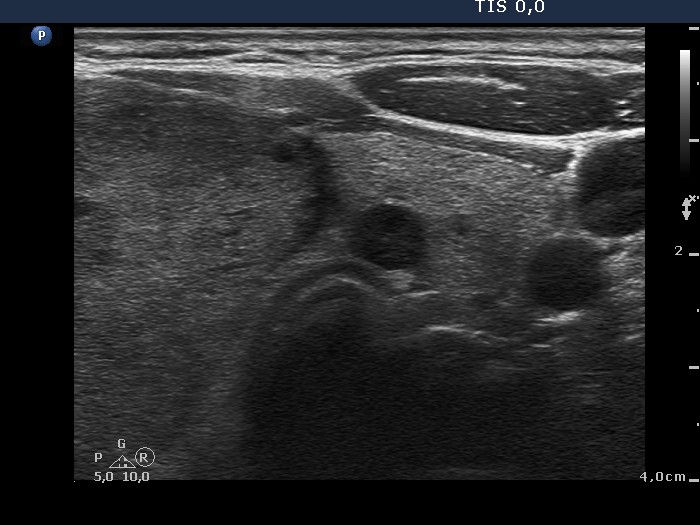

Isthmus and the left lobe, transverse view. This lobe had multiple discrete lesions.